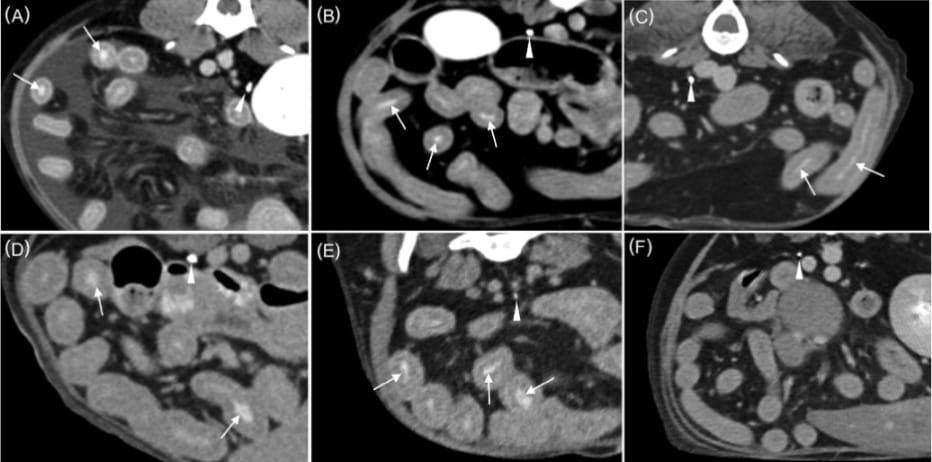

Transverse plane CT images on delay-phase following administration of contrast medium in six dogs suspected or confirmed PLE. Dog1 (A), dog 2 (B), dog 3 (C), dog 4 (D), dog 5 (E), and dog 6 (F). Ureteral contrast enhancement of the excretory phase can be observed (arrowheads). Notethe intraluminal opacification of multiple segments of the small intestine in five dogs (A–E) (arrows) compared to that in dog 6.4 of 7 Veterinary Radiology & Ultrasound, 2025

Intestinal VCME was observed in 5 of 6 dogs diagnosed with PLE, but not in the 24 control dogs without enteropathy. One control dog showed VCME into the cisterna chyli. The association between PLE and intestinal VCME was statistically significant (p < .001). Imaging findings among PLE dogs included intestinal wall thickening, lymphadenopathy, ascites, and pleural effusion. Histological diagnoses in four dogs included lymphoplasmacytic enteritis with lymphangiectasia. No dogs with azotemia or urinary obstruction exhibited intestinal VCME, indicating that the phenomenon was not associated with renal impairment in this cohort.